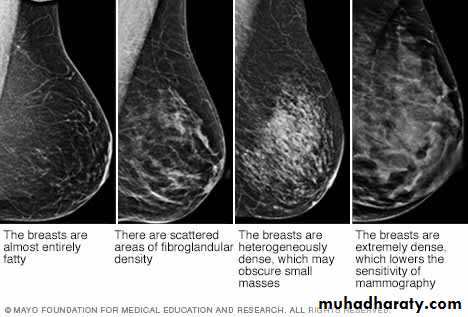

Essentially, breast density is a comparison of the relative amounts of fat versus fibroglandular tissues in the breast.

There are four levels of breast density in keeping with relative increases in the amount of levels of fibro-glandular tissue. These are: